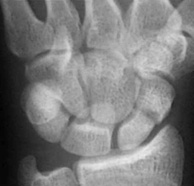

A scaphoid fracture; is a break in the scaphoid bone.  The scaphoid is one of the most important bones in the wrist however it has a poor blood supply.  If a scaphoid fracture is not  treated properly, problems can result in the future, typically arthritis and loss of motion.  The wrist is made up of eight bones (carpal bones) and arranged in two rows between the radius, ulna and the hand bones.  The scaphoid is important because it spans between both of these rows of carpals, stabilising motion between the hand and the forearm.

A scaphoid fracture is a serious problem that may be confused with a wrist sprain. Special X-rays are needed to identify scaphoid fractures; however, some fractures may not be visible on x-ray until a few weeks after the injury. So if the scaphoid is tender on examination but the x-ray shows no fracture x-rays should be repeated after 2 weeks. Rarely a bone scan, MRI or CT scan may be required.